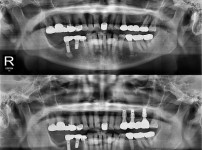

种植牙

局部种植牙